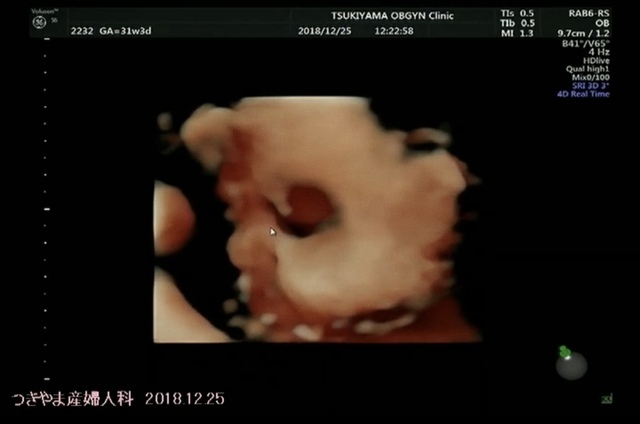

31週3日(31w3d・女の子)|ai635 さん(24歳)

エコー写真撮影時のエピソード:

もう臨月に入りますが、

エコー中きちんと顔が見れたのが

この日のエコーのみ…

後は、ずっと顔を隠しててなかなか見せてくれないから、生まれて顔を見るのが楽しみです!

私の両親は初孫になるので、毎回エコーをワクワクして待っているのですが、最近は顔を見るのを諦めてます。